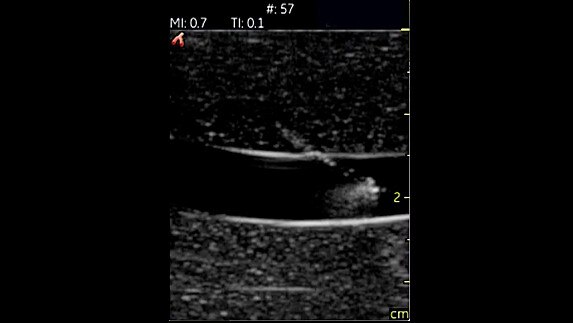

Vascular